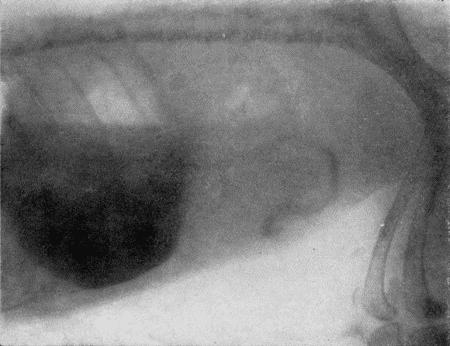

Накачивание воздуха в желудок производят под контролем на просвечивающем экране. В момент, когда баллон с воздухом полностью заполнит желудок и тень печени будет выделяться четко на очень светлом фоне растянутого желудка сзади и на светлом легочном поле спереди, дальнейшее нагнетание воздуха прекращают и вентиль груши закрывают (рис. 167).

В случае беспокойства животного, вызванного чрезмерным растяжением желудка, необходимо часть воздуха выпустить через вентиль. Таким образом, можно установить дозу воздуха, спокойно переносимую животным.

Такой методикой исследования можно обнаружить увеличение печени, изменение конфигурации задней поверхности печени в результате целого ряда патологических процессов, опухоли печени и диафрагмы.